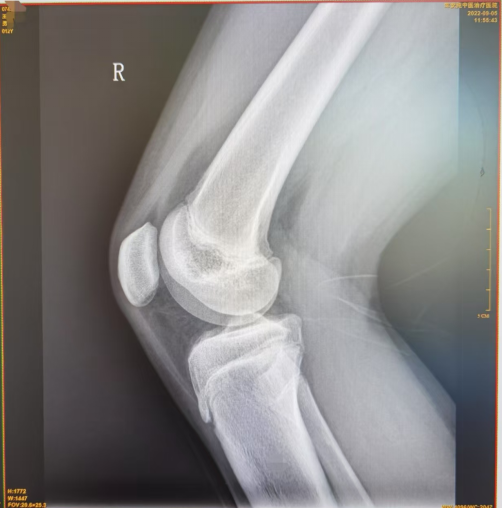

图1可见胫骨结节处无明显损伤,图2可见胫骨结节前缘舌状下缘少许分离,图3可见胫骨结节前缘舌状下缘明显分离且向前凸起。